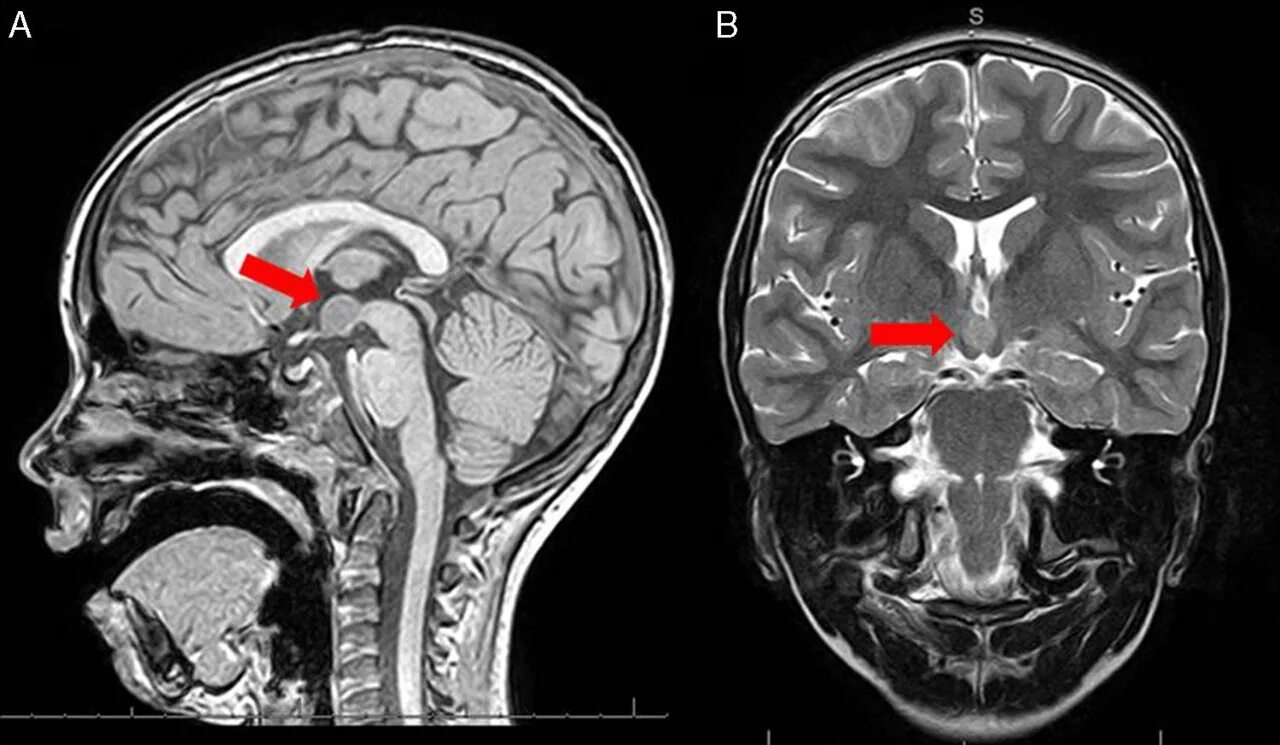

Опухоль гипофиза